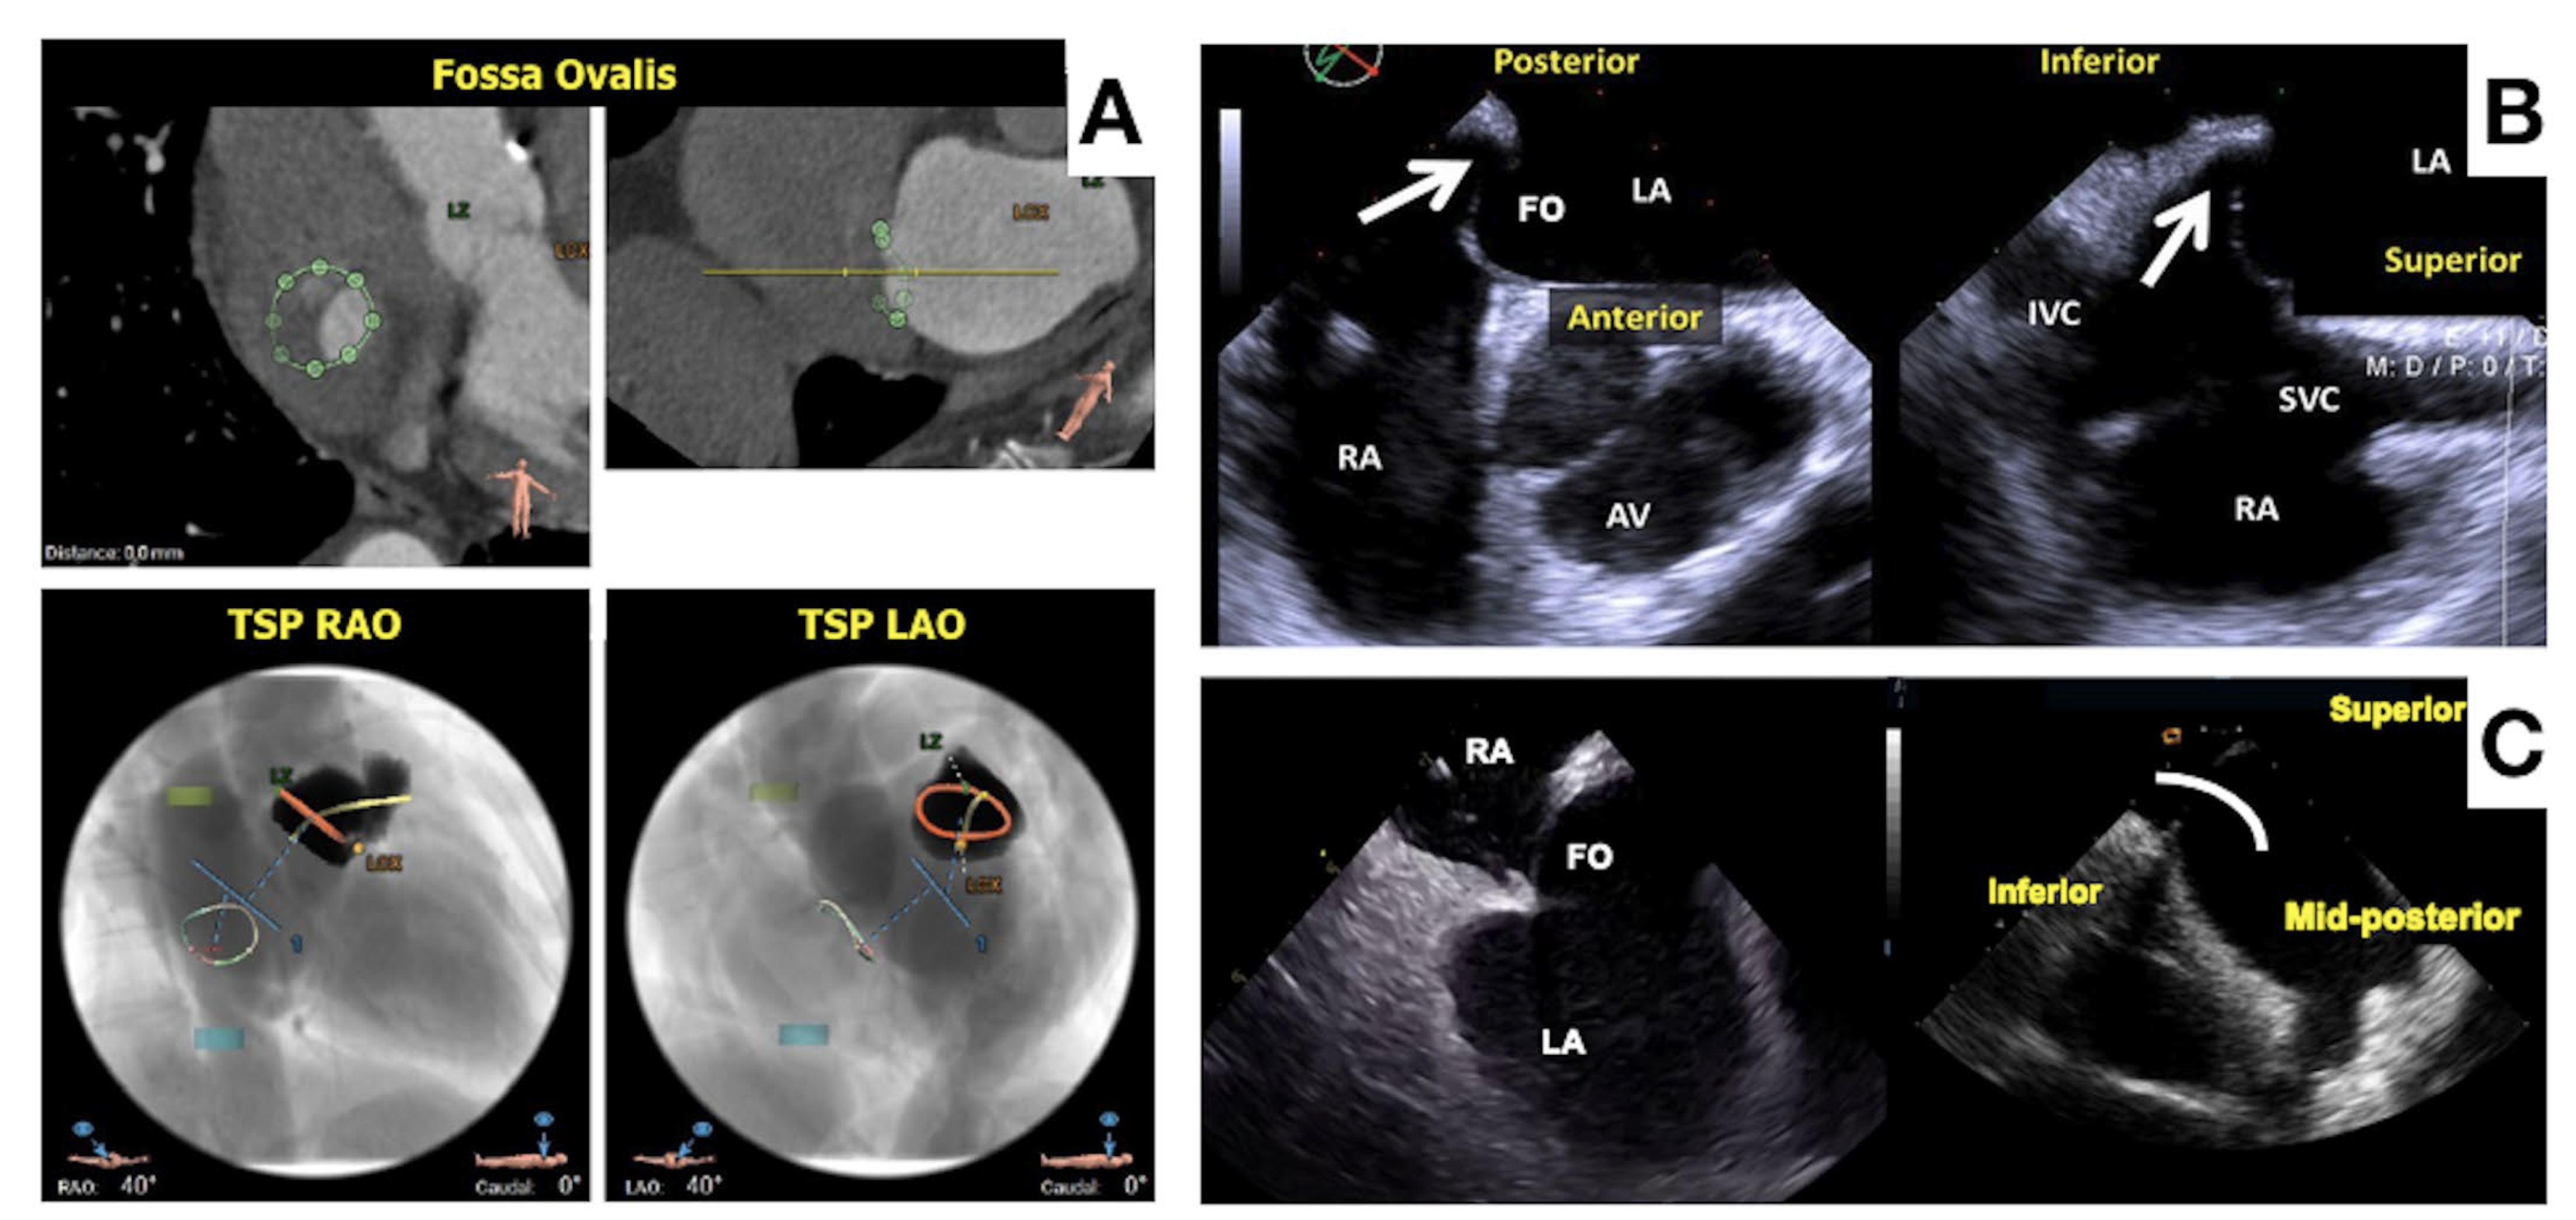

- Fukutomi, M.; Fuchs, A.; Bieliauskas, G.; Wong, I.; Kofoed, K.F.; Søndergaard, L.; De Backer, O. Computed tomography-based selection of transseptal puncture site for percutaneous left atrial appendage closure. EuroIntervention 2022, 17, e1435–e1444. [Google Scholar] [CrossRef]